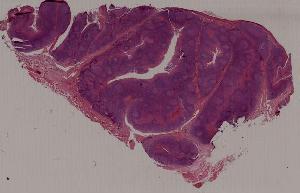

21. Chronic tonsillitis